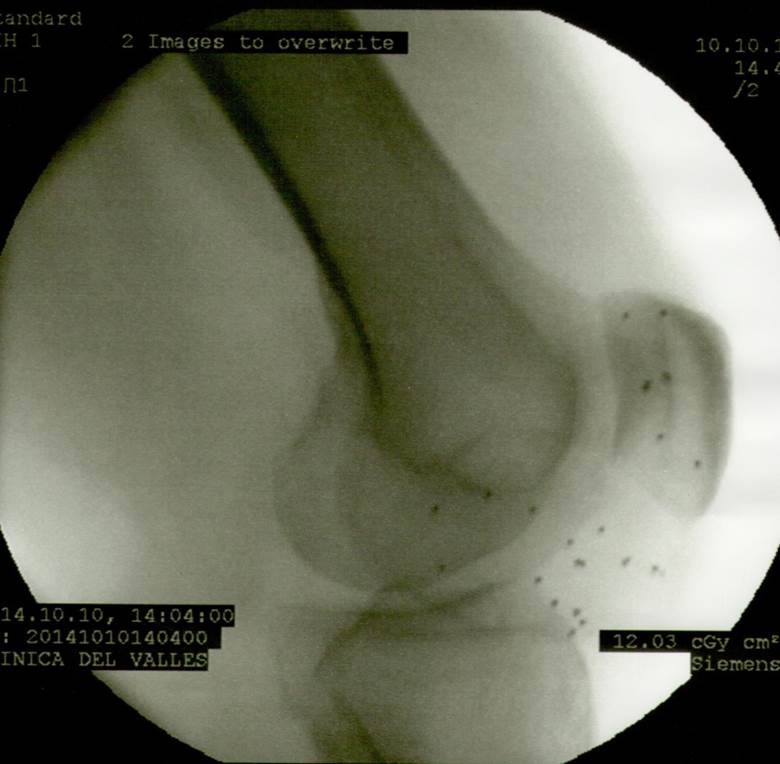

El 10/10/2014 se intervino J.C de 53 años de edad con una necrosis de condilo femoral interno. Desde hacía unos meses realizaba tratamiento de R.F., AINES y marcha con muletas para no efectuar carga de peso con la rodilla afectada. Al examen físico se observaba rodilla con derrame articular, dolorosa a la palpación (especialmente en interlínea interna femorotibial, coincidente con la necrosis), y posición viciosa en flexión. Evitaba la carga de peso por prescripción médica.

A continuacion se observan las imágenes más significativas: